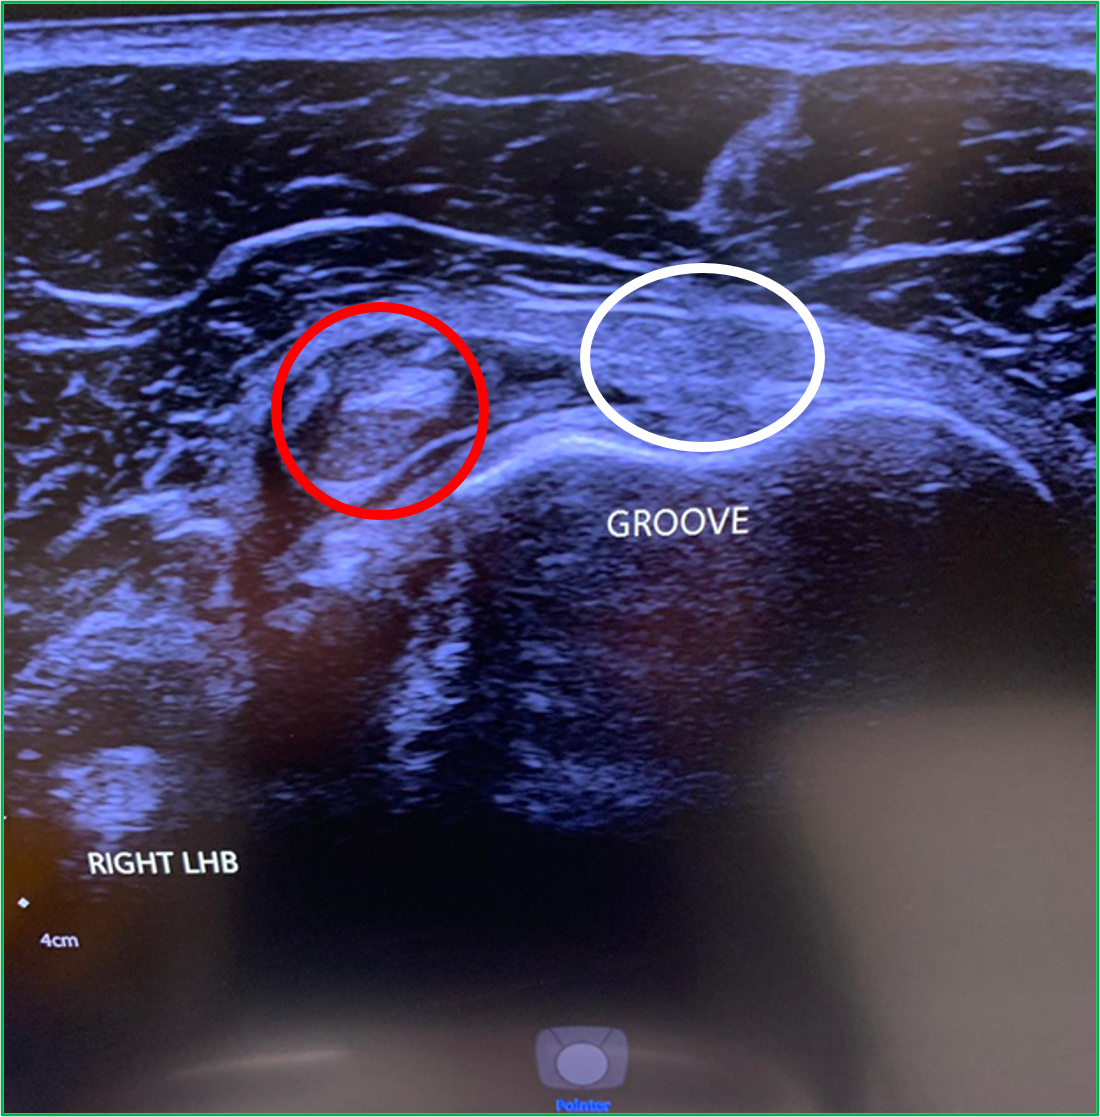

LHB subluxation can happen with contact sports, weight lifting and bodybuilding.

Sometimes the biceps tendon can pop out of its groove. This usually happens because of a tear of the overlying ligament. In other cases, some people are just born with a particularly shallow bicipital groove which puts the tendon at risk of subluxing under load.

Ultrasound findings are of a tendon that is not correctly sited in the bicipital groove (Red circle. The white circle shows where the LHB should sit). To find out more about LHB subluxation: